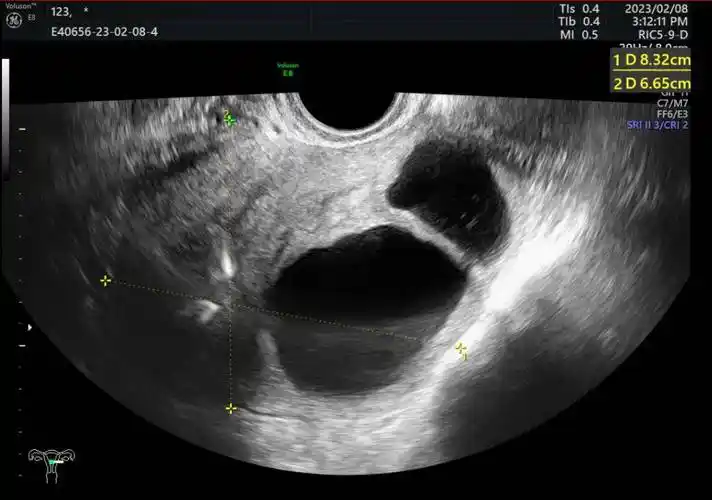

病例分享:子宫间皮囊肿 1 例_回声_cm_超声